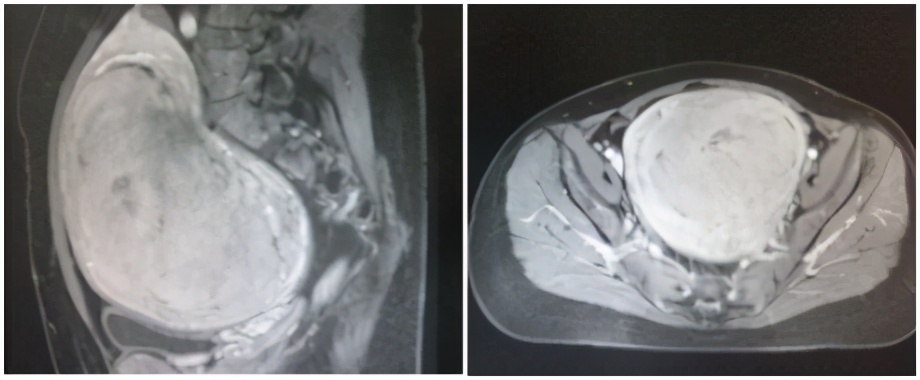

事实:用海扶刀®设备来进行子宫肌瘤的聚焦超声消融治疗,因聚焦超声消融的温度可达65℃及以上,能使细胞产生不可逆的凝固性坏死,因此通常只需单次治疗。而与聚焦超声消融有相似之处但是又有着本质不同的聚焦超声热疗,因温度低于60℃,细胞只是损伤,因此需多次治疗。

(子宫肌瘤7*6cm,应用海扶刀®设备一次性消融治疗)